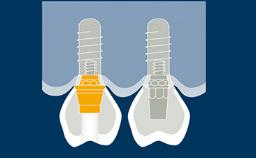

In modern implant dentistry, the overall esthetic result is of equal or greater importance to the patient. Esthetic results are closely related to a high level of accuracy in the positioning of the supporting dental implants.

Templates to guide accurate three-dimensional implant placement are critical to achieving such an outcome. This ITI Learning Module will discuss routine use of templates in implant therapy.